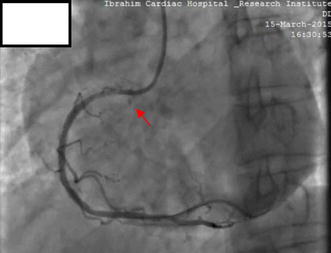

Following CAG, he was selected for angioplasty of the RCA. The RCA was easily cannulated with a soft tipped 6-French JR 3.5 guiding catheter (USA). After the selection of the guiding catheter in the RCA, a 0.014 in. Asahi Sion Blue PTCA guide wire (Asahi Intecc Co., Ltd., Japan) was advanced to cross the lesion. Pre-dilatation was done by 2.5 × 15 mm Sapphire balloon at an inflation pressure of 12 atmospheres (ATM) for 10 s. Stenting was done by 2.75 × 38 mm novolimus-eluting DESyne stent (Elixir medical corporation, Sunyvale, CA) at 16 ATM for 20 s, with restoration of thrombolysis in myocardial infarction (TIMI) III flow. At this point we observed an Ellis type II perforation in the ostial RCA, as evidenced by subtle contrast (Fig. 2; Additional file 1: Video S1). The next contrast injection given very gently showed that the perforation had extended into the right coronary sinus of Valsalva, as evidenced by contrast dye beyond the RCA ostium and retrograde stasis limited to the sinus of Valsalva (Fig. 3; Additional file 2: Video S2). There was no rupture of the balloon. Despite coronary perforation, the patient remained haemodynamically stable, reported no chest discomfort and electrocardiogram showed no sign of new ischemia. Urgent cath lab TTE showed no pericardial effusion or aortic regurgitation (AR). Serum cardiac enzymes and troponin I were within normal range.

Fig. 2.

Coronary angiography following stenting of RCA lesion. Stenting was done by 2.75 × 38 mm novolimus-eluting DESyne stent at 16 ATM for 20 s, with restoration of thrombolysis in myocardial infarction (TIMI) III flow. An Ellis type II perforation is noted in the ostial RCA, evidenced by subtle contrast (red arrow)